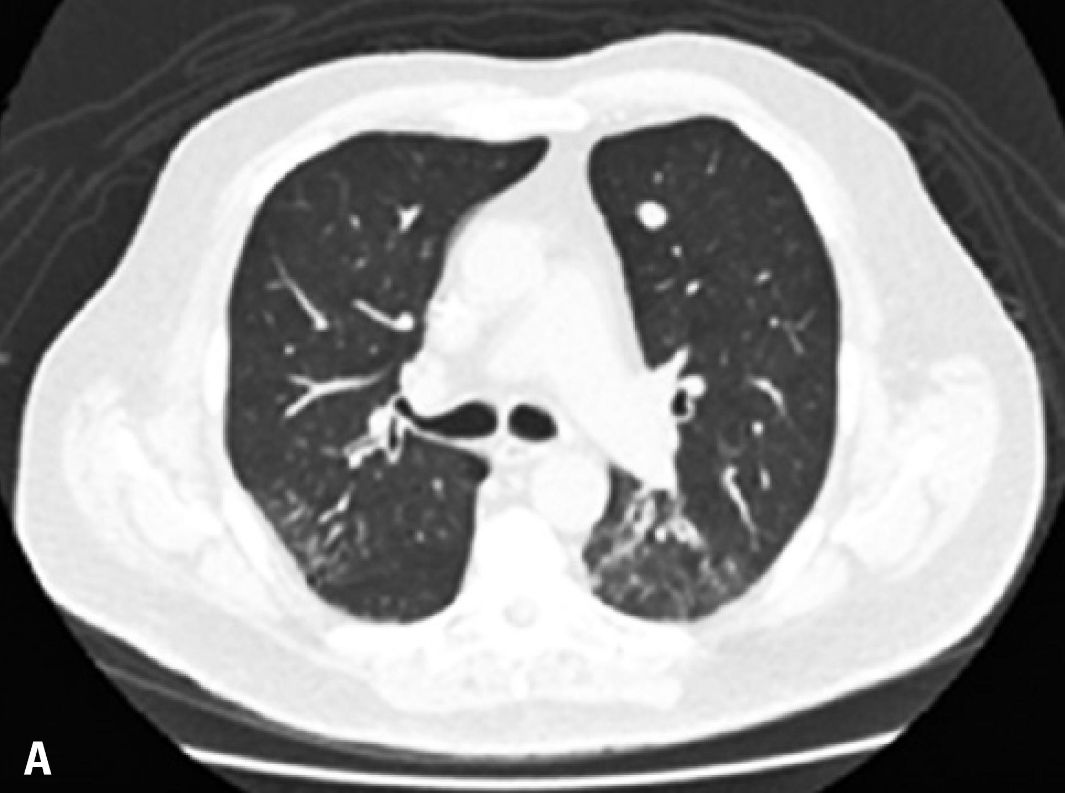

患者是一名73岁的老年男性,左大腿存在黑色素瘤病灶。病人在发病早期就接受了局部切除治疗,并在日后的过程中坚持随访。直到术后第8年,病人检查出了肺部的黑色素瘤转移病灶,其开始使用达卡巴嗪和伊匹木单抗进行治疗,但是病情的进展过程并没有被抑制,因此,病人开始使用帕博利珠单抗每3周2mg/kg的方案进行治疗。但是在第一次治疗后的14天时,病人开始出现干咳(无其他症状),CT检查显示其双侧肺部都出现了磨玻璃样改变。病人被确诊为帕博利珠单抗导致的肺炎,并迅速接受了1mg/kg强的松联合抗生素的治疗,万幸的是病人的肺部症状在用药治疗后出现 了明显的好转。2个月后,病人的肺部炎症反应被完全治愈,并对持续进行的帕博利珠单抗治疗表现出了良好的耐受性。